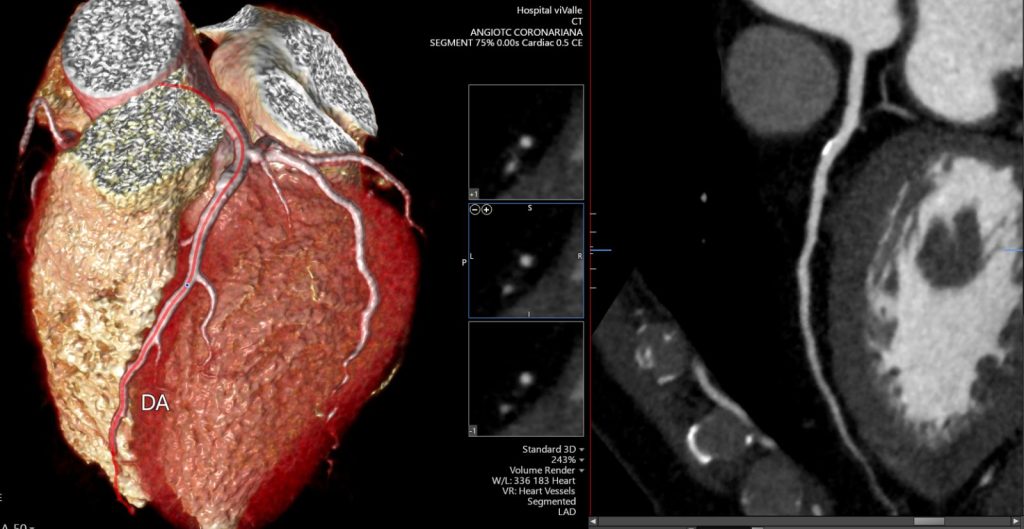

A angioTC de coronárias (CCTA) vem ganhando protagonismo na prevenção primária porque vai além do escore de cálcio: ela identifica placas não calcificadas, muitas vezes invisíveis ao CAC, e que podem representar aterosclerose ativa e risco real mesmo em pessoas classificadas como “baixo risco” pelos escores tradicionais.

Um grande estudo populacional recente (JAMA), com quase 25 mil indivíduos de 50 a 64 anos sem doença cardiovascular conhecida e seguimento de aproximadamente 8 anos, mostrou que a presença de placa não calcificada na CCTA se associou a maior risco de primeiro evento coronário e que a inclusão dessas informações anatômicas melhorou a predição de risco e a reclassificação, principalmente entre os pacientes inicialmente rotulados como baixo risco.

Na prática, isso muda o jogo: detectar precocemente placas não calcificadas permite “antecipar” o diagnóstico da doença coronária, individualizar a prevenção e orientar medidas mais assertivas — especialmente em pacientes que, pelo cálcio ou pelo risco clínico, poderiam ser falsamente tranquilizados.